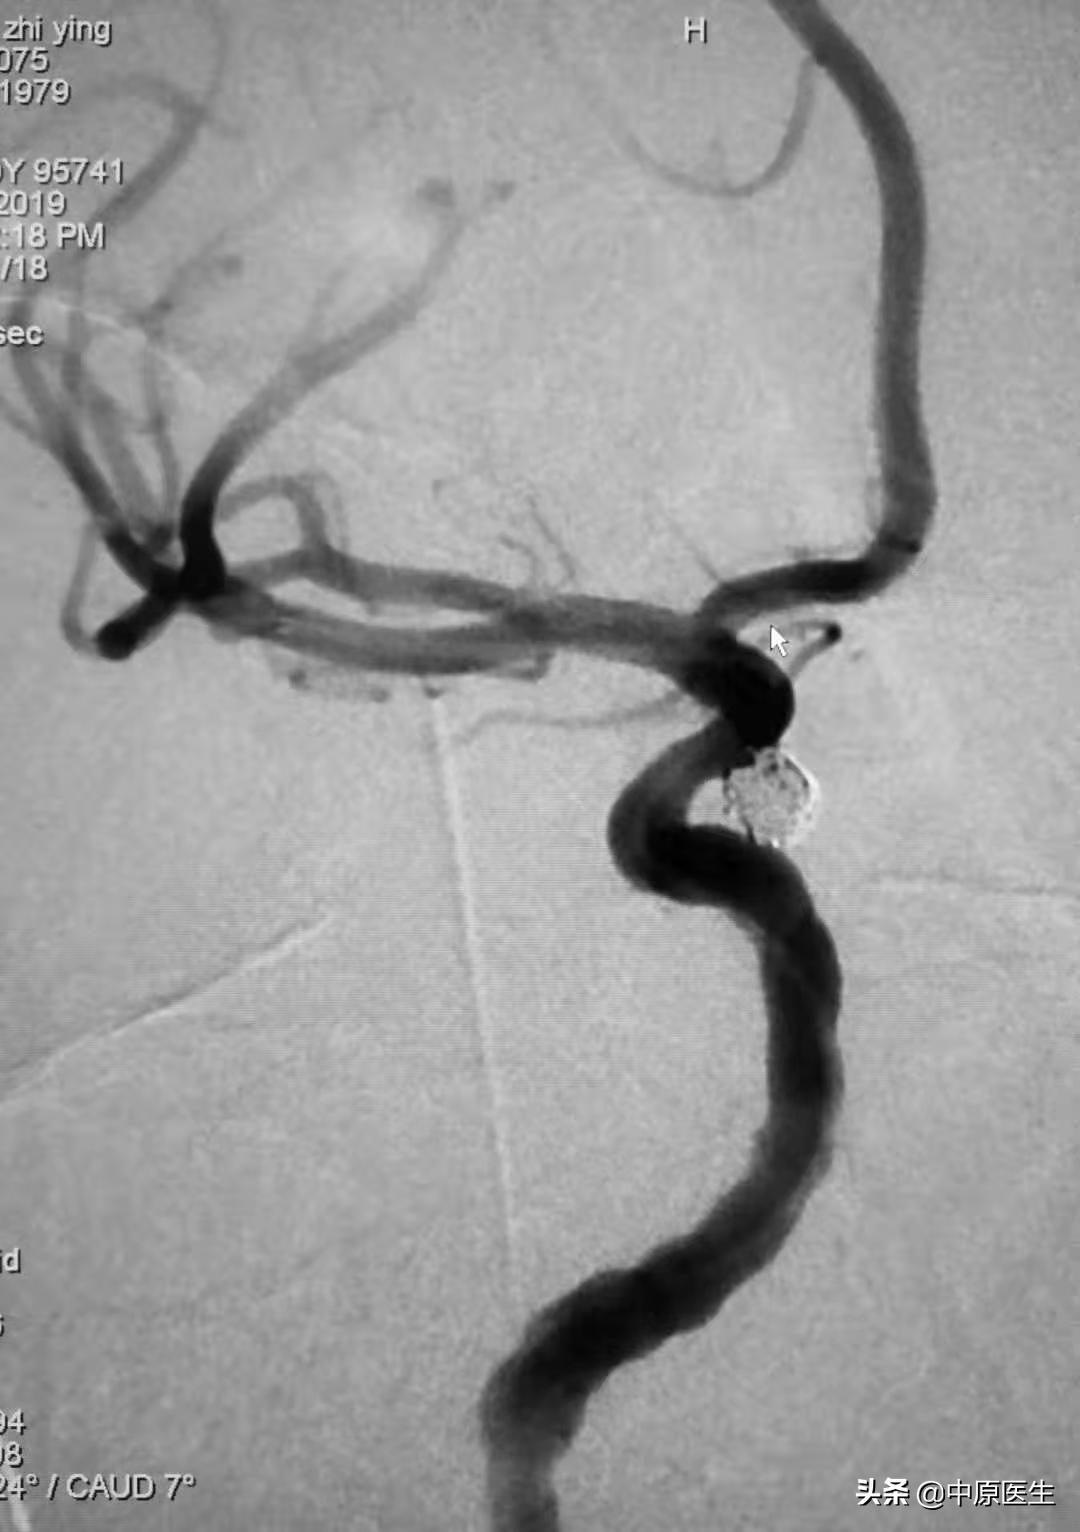

动脉瘤直径 3.8mm×4.2mm, 我建议第一个弹簧圈选择 6mm×15cm 的规格,可是 赵小源不听话,选了一个 6mm×20cm 的弹簧圈。(见图7~9)

结果,一个弹簧圈就把手术结束了。